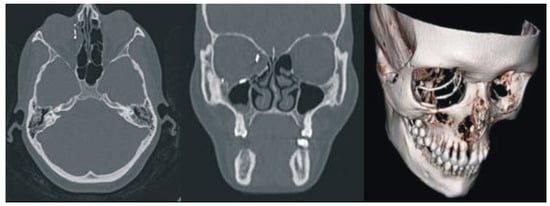

No major complications were observed in the postoperative period. Moderate retrobulbar edema was observed in the early postoperative period. The conjunctival fold up to 2 mm in thickness was seen on the bulbar conjunctiva at the 6 o’clock position. In the early postoperative term, binocular diplopia occurred in various positions of gaze. This might have been caused by edema and postoperative retrobulbar hematoma. A month later, clinical examinations and spiral CT scans with 3D reconstruction as depicted in Figure 3, indicated that the eyeball position in the repaired orbit symmetrically matched that of the intact side. The location of KTNM was the same as intraoperatively predetermined. The patient demonstrated the full range of movement of the eyes. There was no evidence of diplopia. Postoperative ophthalmologic findings are also given in Table 1, whereas the patient appearance six months after surgery is illustrated in Figure 1b.

Figure 3. Facial CT images with 3D reconstruction at one month after surgery.